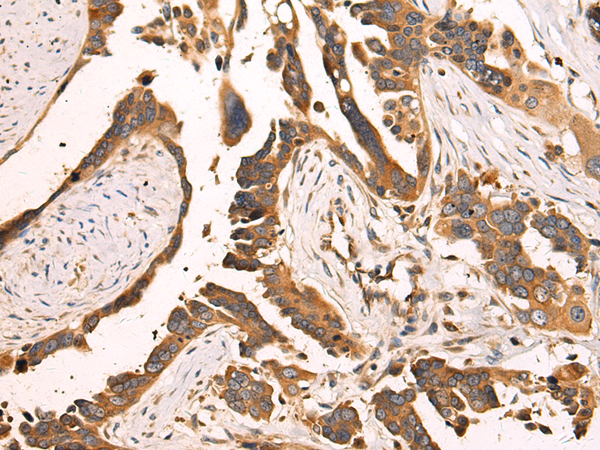

IHC positive control: |

Human colorectal cancer |

IHC Recommend dilution: |

100-200 |